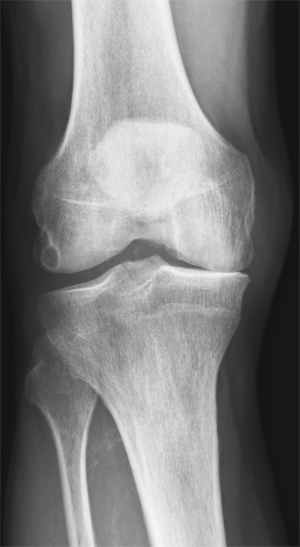

For ti år siden fikk jeg besøk av en pasient med store plager fra artrose i det ene kneet. Han hadde tatt røntgenbilde av kneet og fått vurdering av ortoped, som konkluderte med at det var så stor artrose at protese var eneste aktuelle behandling. Pasienten var fysisk svært aktiv, både på ski og med fotturer i fjellet, og var lite innstilt på proteseoperasjon. Han kjente til at jeg hadde lang erfaring med behandling av idrettsutøvere med plager fra muskler og ledd, og ba om time, selv om han ikke var en av mine ordinære pasienter.

En «vanlig sykehistorie» med artrose i hofte og kne i Norge er klinisk undersøkelse, røntgenundersøkelse, smertestillende og henvisning til 12 – 15 behandlinger hos fysioterapeut. Dersom det fortsatt er mye plager, henvises pasienten til vurdering for proteseoperasjon.